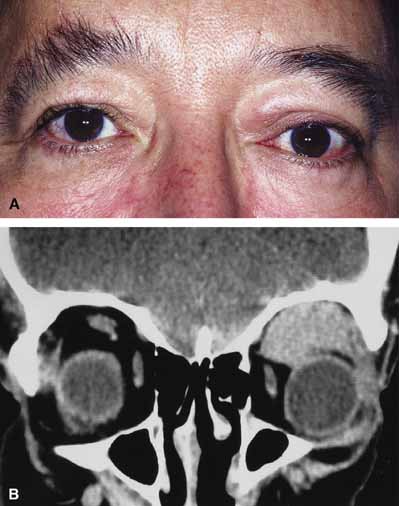

In some patients the orbitopathy is more aggressive and rapidly evolving with acute proptosis over 1 to 2 days, swelling of the lids and conjunctiva, diplopia, corneal exposure, and optic neuropathy (Fig. 6A). This presentation may be confused with disorders such as nonspecific orbital inflammation or carotid-cavernous fistula.44 The differential diagnosis of acute proptosis with enlarged extraocular muscles includes thyroid orbitopathy, vascular causes (arteriovenous fistulas), inflammation (orbital myositis, sarcoid), infection, primary invasive tumor, metastasis to the extraocular muscles.45,46

Fig. 6 A. A 56-year-old female presented with a 2-day history of proptosis, lid swelling, conjunctival chemosis/injection, and double vision. Thyrotropin (TSH) level was extremely low and a computed tomography (CT) scan revealed grossly enlarged extraocular muscles. A diagnosis of acute thyroid eye disease was made. B. Axial computed tomographt (CT) scan illustrating diffuse enlarged extraocular muscles characteristic of thyroid eye disease. C. Coronal computed tomography (CT) scan showing enlargement of extraocular muscles.

Thyroid orbitopathy usually occurs close to or within 18 months of the hyperthyroid state.39 Some patients will be hyperthyroid at the time of diagnosis, others euythyroid, and some might even be hypothyroid. The hyperthyroid state is characterized by elevation of the plasma thyroid hormones triiodothyronine (T3) and thyroxine (T4). For patients presenting primarily with features of thyroid orbitopathy and no clinical thyroid abnormality, the laboratory investigations should include sensitive thyrotropin (TSH); free T4 or total T4 (if TSH is low or altered); T3 (if TSH is low); and normal T4 testing. Additional tests that may be of benefit include thyroid antibody titer and TSH receptor antibody test.

CT classically reveals enlarged extraocular muscles (Fig. 6B and 6C). One or all of the muscles may be involved and there is bilateral involvement in the majority. The most frequently involved muscle is the inferior rectus followed by the medial, superior, and lateral rectus (opposite to the spiral of Tillaux).40 The tendons of the affected recti muscles are typically not thickened, resulting in a characteristic fusiform enlargement of the muscle, whereas in myositis secondary to nonspecific orbital inflammation the tendons are generally thickened. Other signs are also useful to distinguish between the two. Bilaterally is unusual in myositis but common with thyroid. Thyroid usually has several muscles involved while myositis more often only has one muscle involved. In myositis the muscle border is more likely to be irregular or fuzzy with or without involvement of adjacent fat whereas in thyroid disease the muscle border is regular and there is no fat involved. Clinically there are also several distinguishing features. Myositis classically presents more rapidly and is associated with pain on extraocular movement. This is rare with thyroid eye disease. The eyelid signs (retraction, flare) are common with thyroid but absent in myositis.